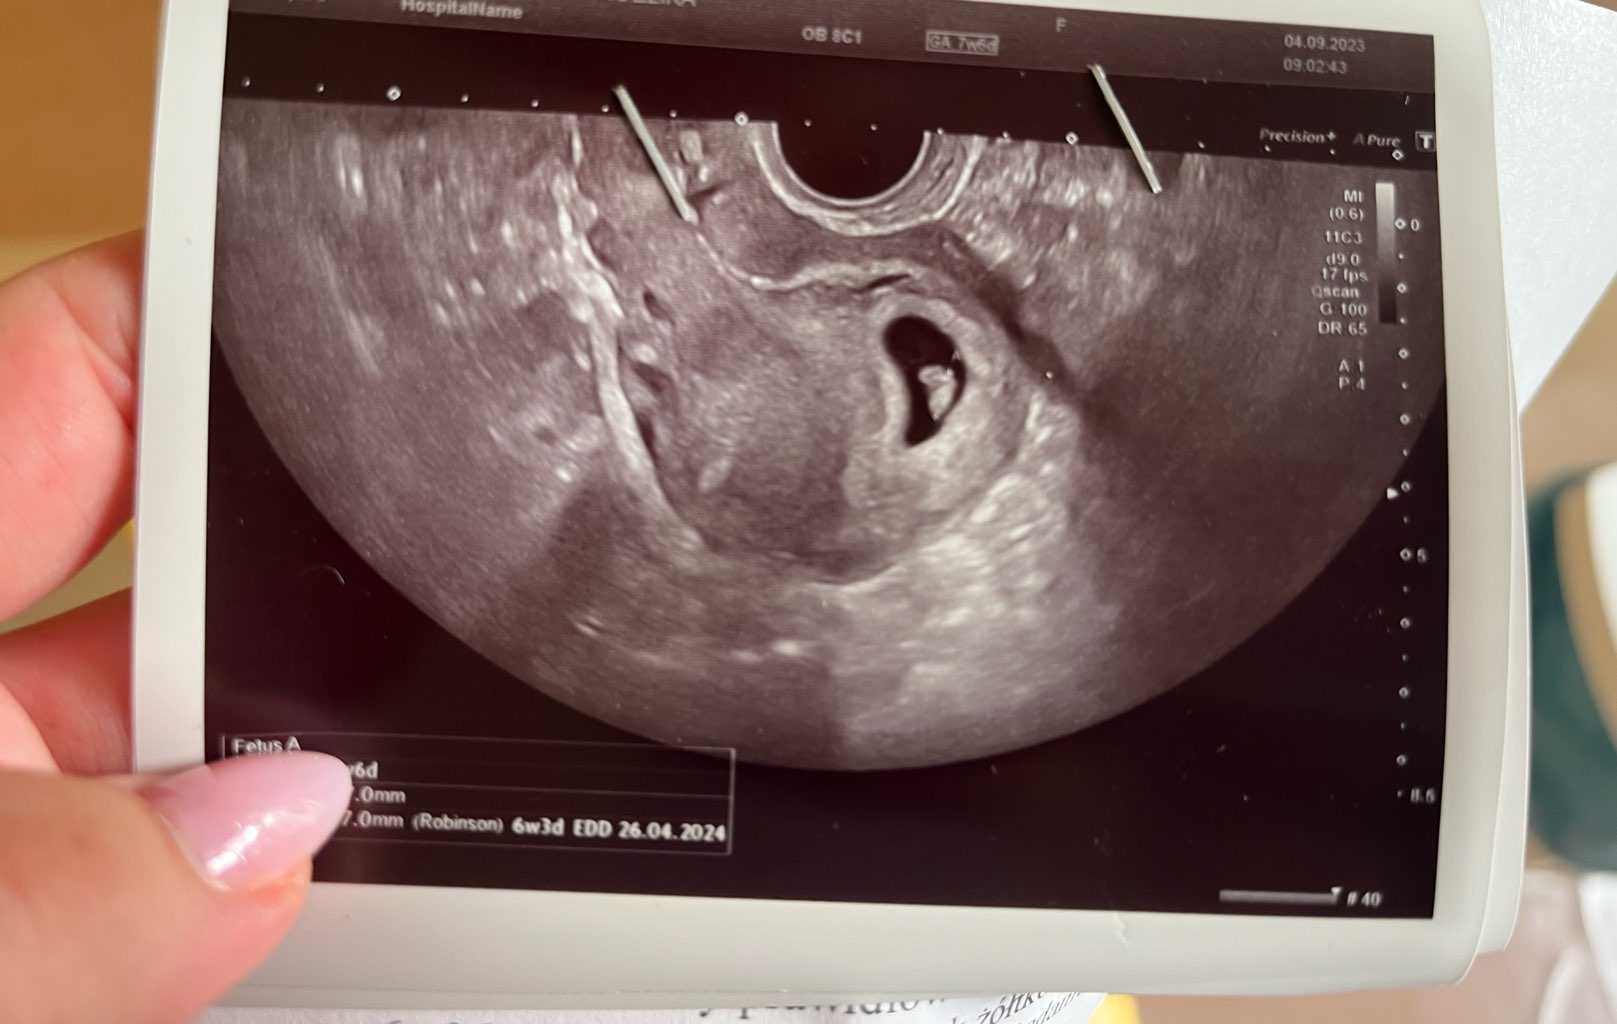

Dziewczyny, wszystko jest dobrze. Widziałam bijące serduszko.

Lekarz nic nie mówił o hormonach i krwinkach, wszystko było tez ładnie widać. Nie wiem czy dalej mam brać te hormony w związku z tym bo dostałam je od innego lekarza ale chyba nie można tak schodzić z hormonów od razu

• IMG_1548.jpeg

IMG_1548.jpeg

145,7 KB · Wyświetleń: 91